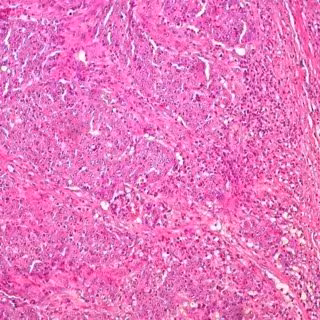

Utilizando melanoma humano y líneas celulares de cáncer de mama, y ??luego validando los hallazgos en modelos de ratón, los científicos encontraron que la terapia modificada de poliovirus comienza uniéndose a células malignas, que tienen una abundancia de proteína CD155. La proteína CD155 también se conoce como el receptor del poliovirus. Entonces, el virus modificado comienza a atacar las células tumorales, matando directamente muchas, pero no todas. Esto libera antígenos tumorales.

La segunda fase de asalto es más complicada. Al matar las células cancerosas, el poliovirus modificado desencadena una alarma dentro del sistema inmunológico, alertando a las defensas del cuerpo para ir al ataque, lo cual parece ocurrir cuando el poliovirus modificado infecta las células dendríticas y los macrófagos. Entonces, las células dendríticas presentan el tumor a las células T para lanzar una respuesta inmune.